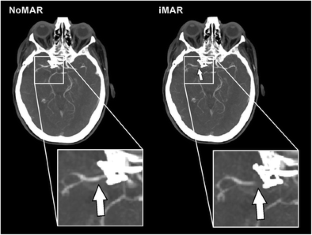

Intracranial aneurysm with clipping vr coiling: